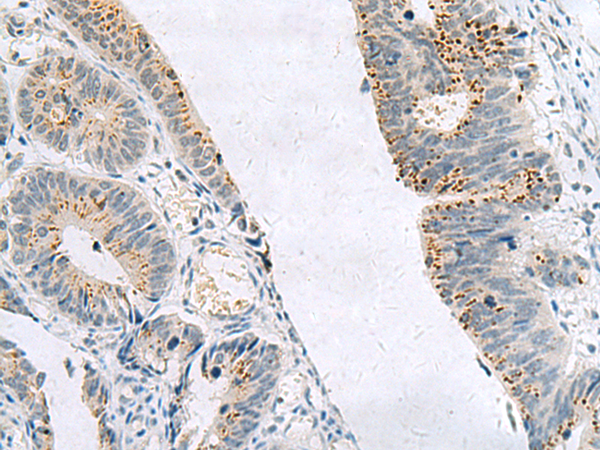

分类: 科研抗体货号: P10690别名: TIM; KIM1; TIM1; CD365; HAVCR; KIM-1; TIM-1; TIMD1; TIMD-1; HAVCR-1应用: WB,IHC反应种属: Human